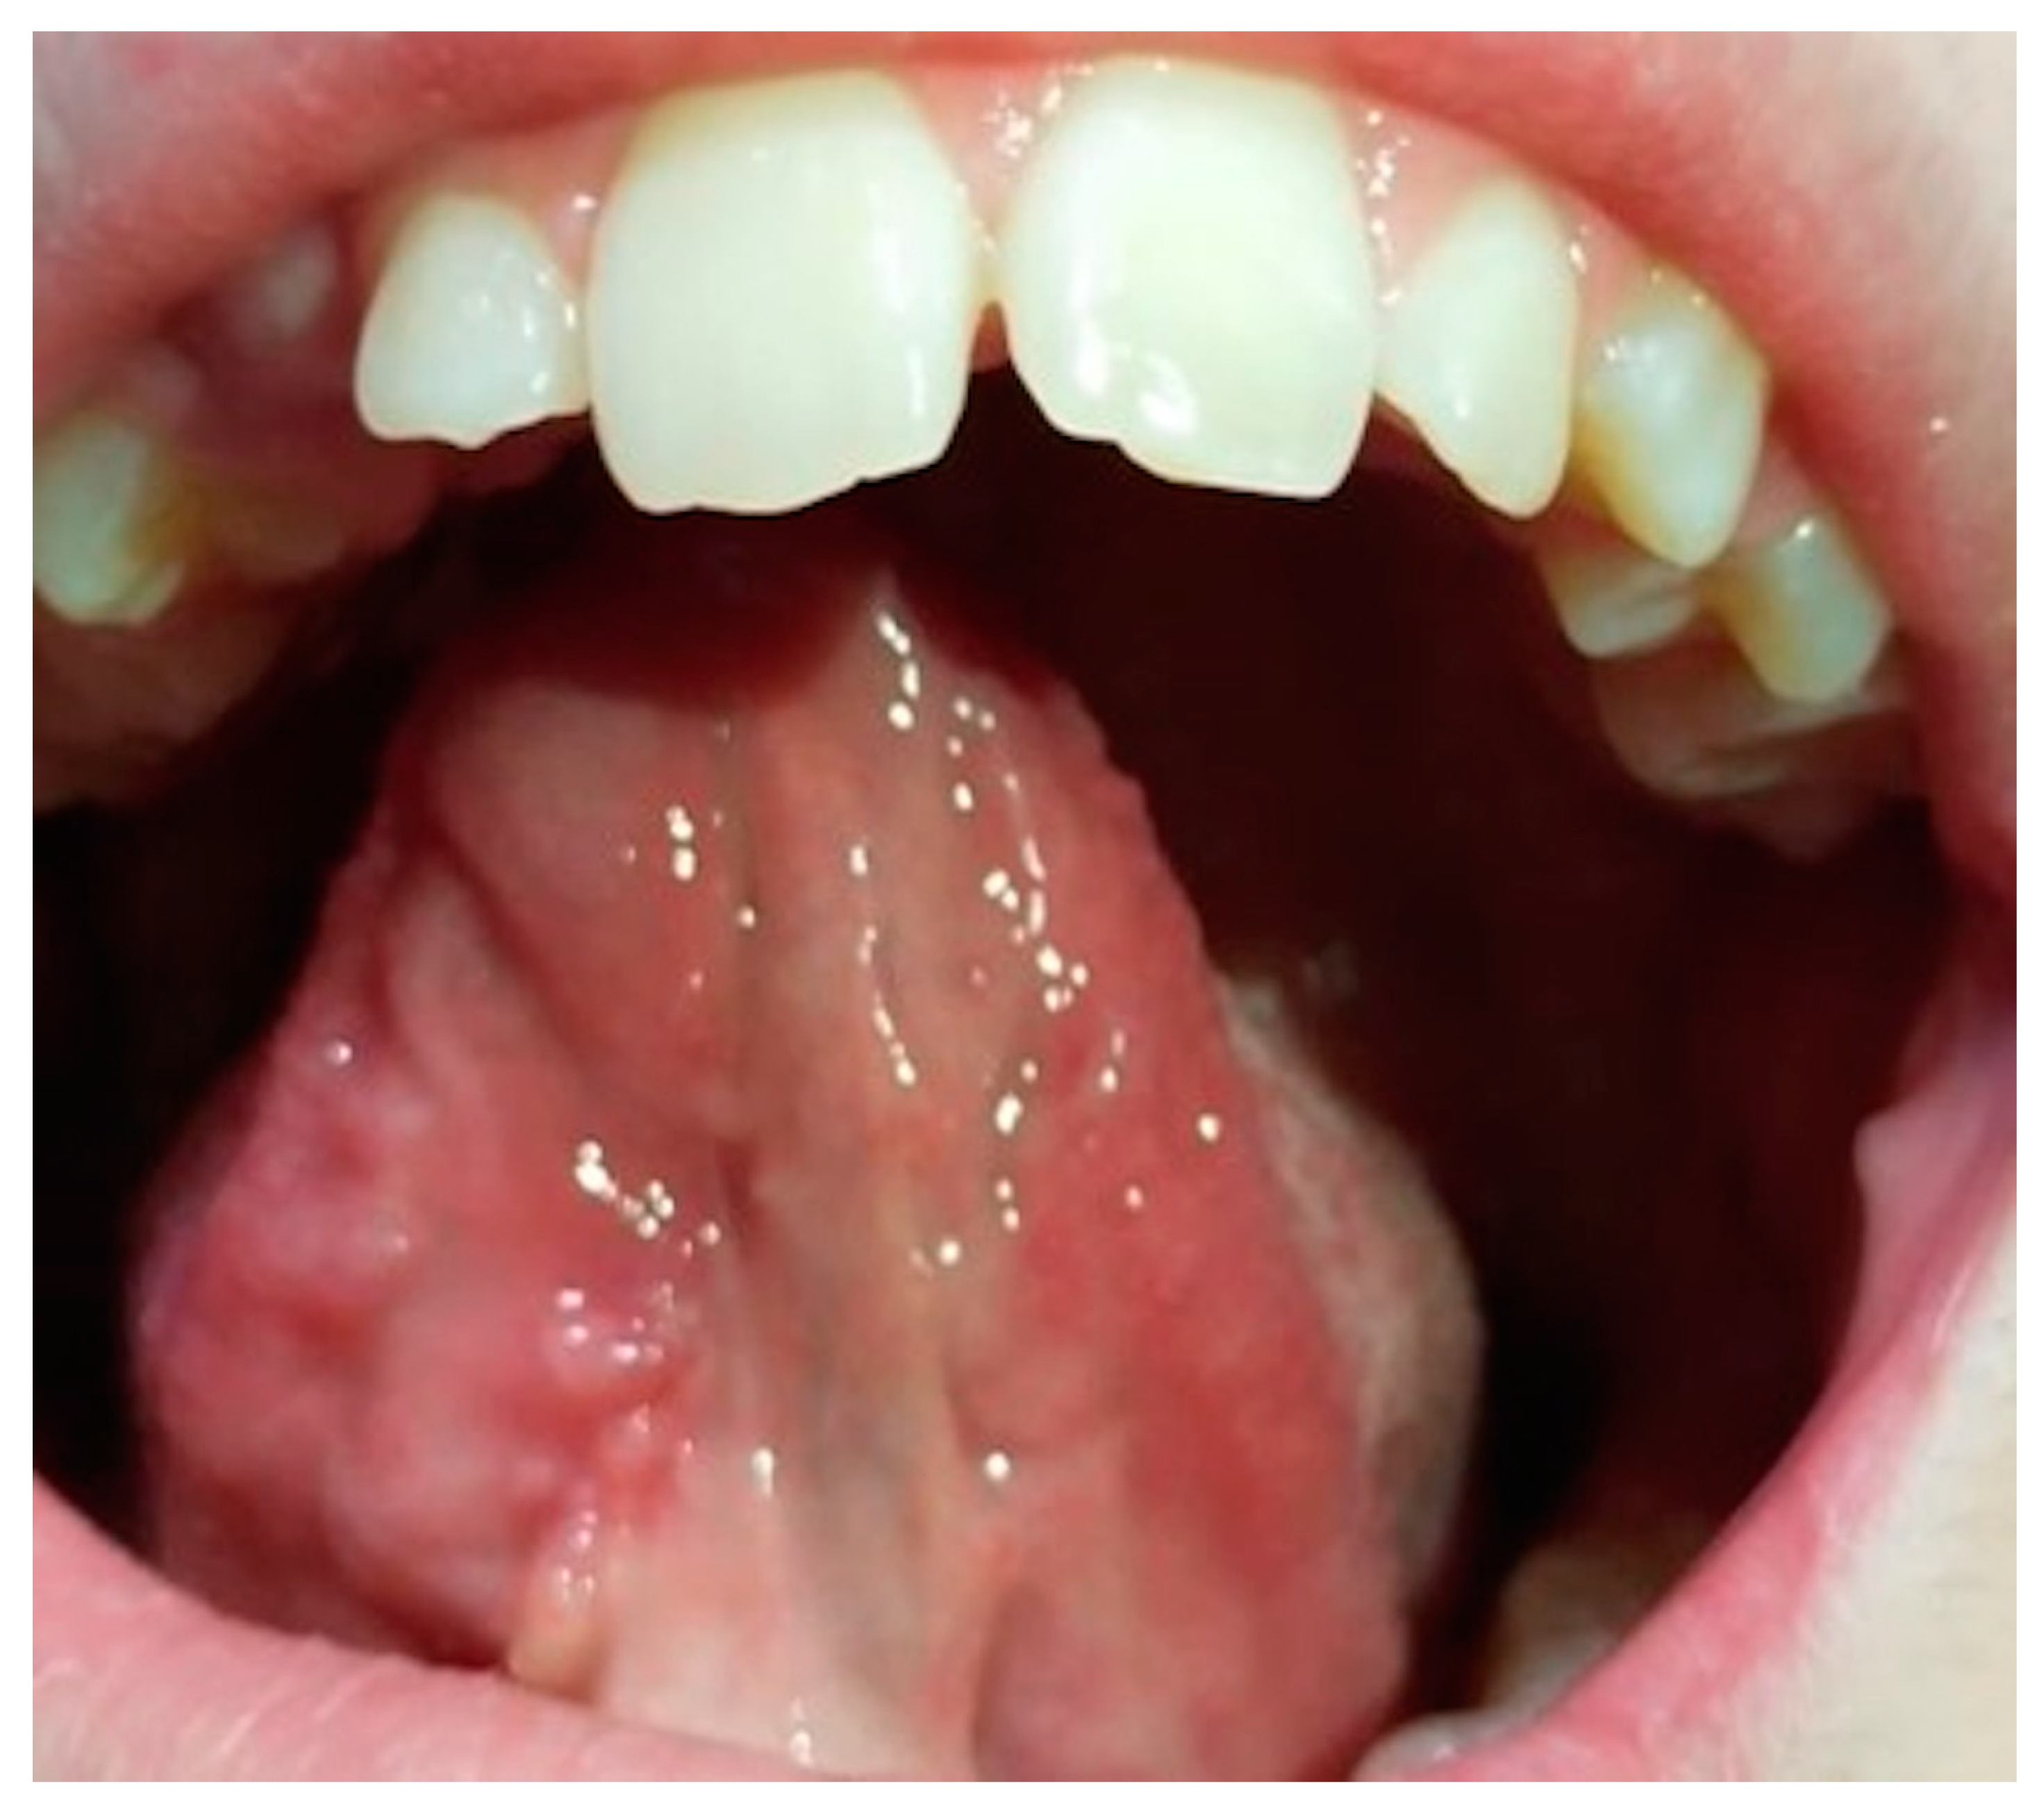

The patient was examined one month after surgery and an area remained inflamed around the resorbable stitches, but showed good healing of the tissues. The patient showed no pain and no decrease in normal tongue function. The images one week later show complete resorption of the suture and an evident improvement of the area that remained swollen (fig.8 and 9).

Figure 8.

Preprints 77661 g008

Figure 9.

Preprints 77661 g009